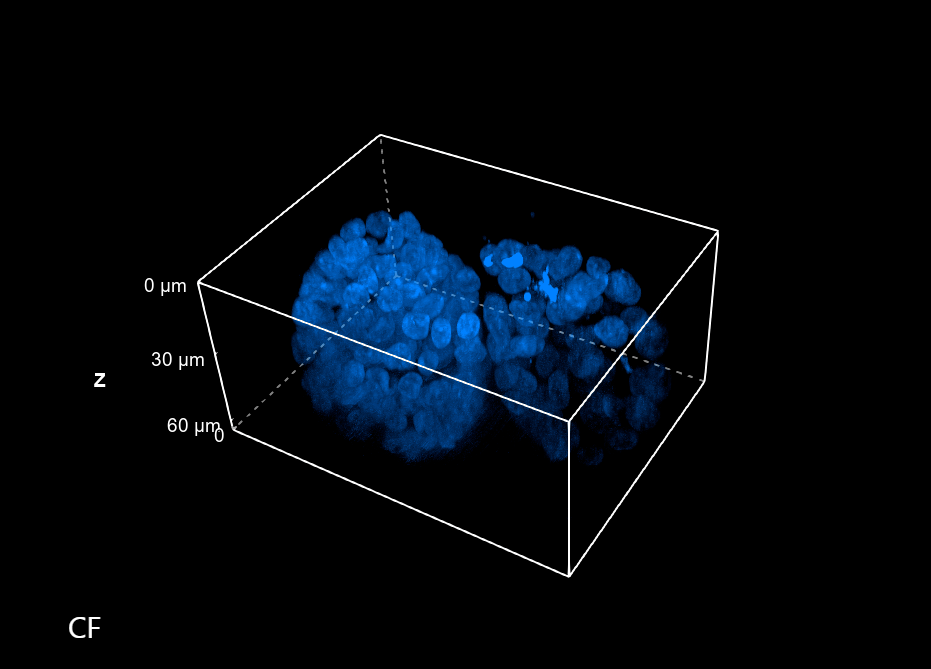

The imaging acquisition technology behind HCI requires a system capable of collecting many images in a short time; however, speed isn’t the exclusive requirement. Indeed, HCI is very often applied to 3D samples that best summarize the correct tissue physiology or pathology. Hence, for this type of application, it is essential to have a system that is also capable of achieving an axial resolution sufficient to resolve complex biological structures properly.

Especially where there is the need to make a morphological study of thick 3D structures, the common Widefield (WF) techniques risk giving an approximate view of the sample. In this context, Figure 1 compares two 60 um thick spheroids acquired with WF and confocal (CF) imaging modalities. It is therefore evident that due to a better Z sampling provided by the CF, two spheroids that otherwise would appear as a single large spheroidal structure can be better resolved and this is crucial when morphological studies are accomplished.

Figure 1: Comparison between WF and CF spinning disk volume views of 60 um spheroids. These images were acquired with a CFI Plan Apochromat Lambda D 60x oil objective (60x, Nikon, 1.42 NA and 0.15 mm WD).